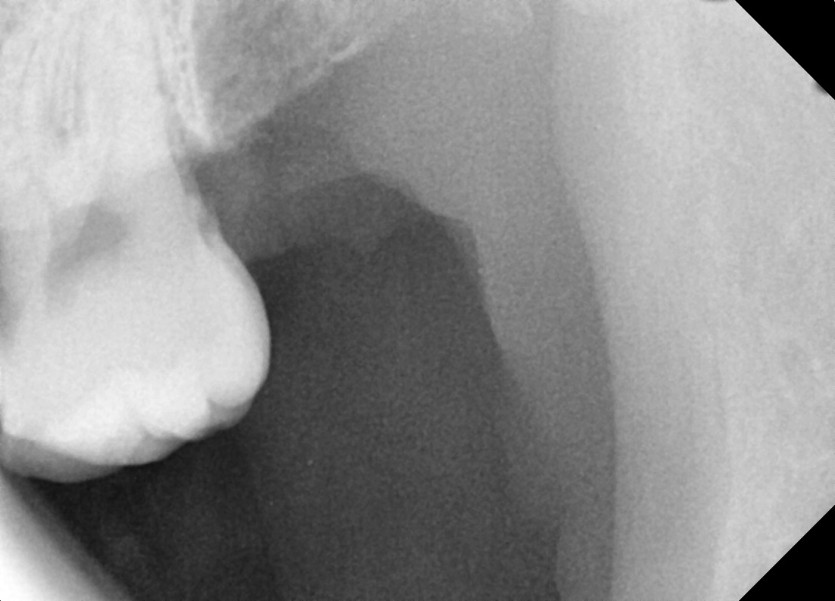

#28,38 사랑니 발치

구강 외과 전문의가 당일 발치했습니다.